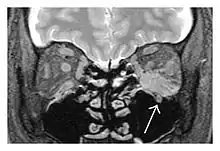

![]() Enlargements in the left inferior rectus muscle and infraorbital nerve (arrow) in a 65-year-old man with a serum IgG4 of 404 mg/dL.[1] (T2-weighted MRI) |